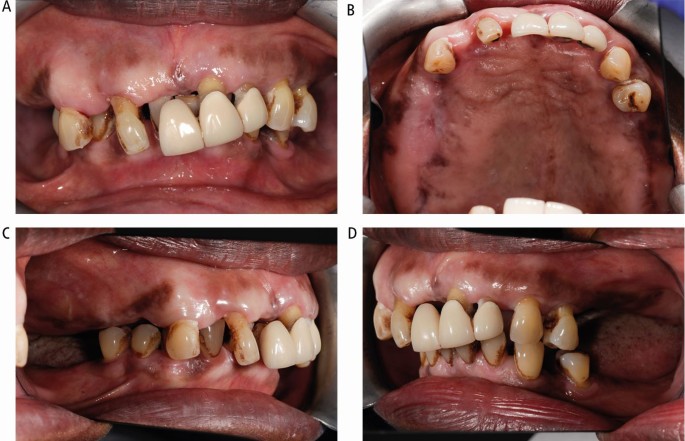

The intra-oral appearance is shown in Figure 10, with the expansion of the right maxillary alveolus causing the occlusal cant. The oral hygiene was poor, with inflamed gingival tissues with bleeding and probing depths of up to 7 mm. The upper anterior bridge was failing with extrusion of the grade III incisor teeth and missing molars with a traumatic overbite.

Case 2: intra-oral views. (A) Right cant with teeth in occlusion. (B) Palatal view showing the bony expansion of the right maxilla. (C, D) Right and left lateral views showing the lack of interocclusal space on the right side

The ‘ground-glass' radiographic appearance of the bone in the right maxilla and mottled appearance in the lower right mandible are evident in Figure 11.

Case 2: orthopantomogram showing the ground-glass and mottled appearance of the alveolar bone (indicated with arrows) and generalised horizontal bone loss